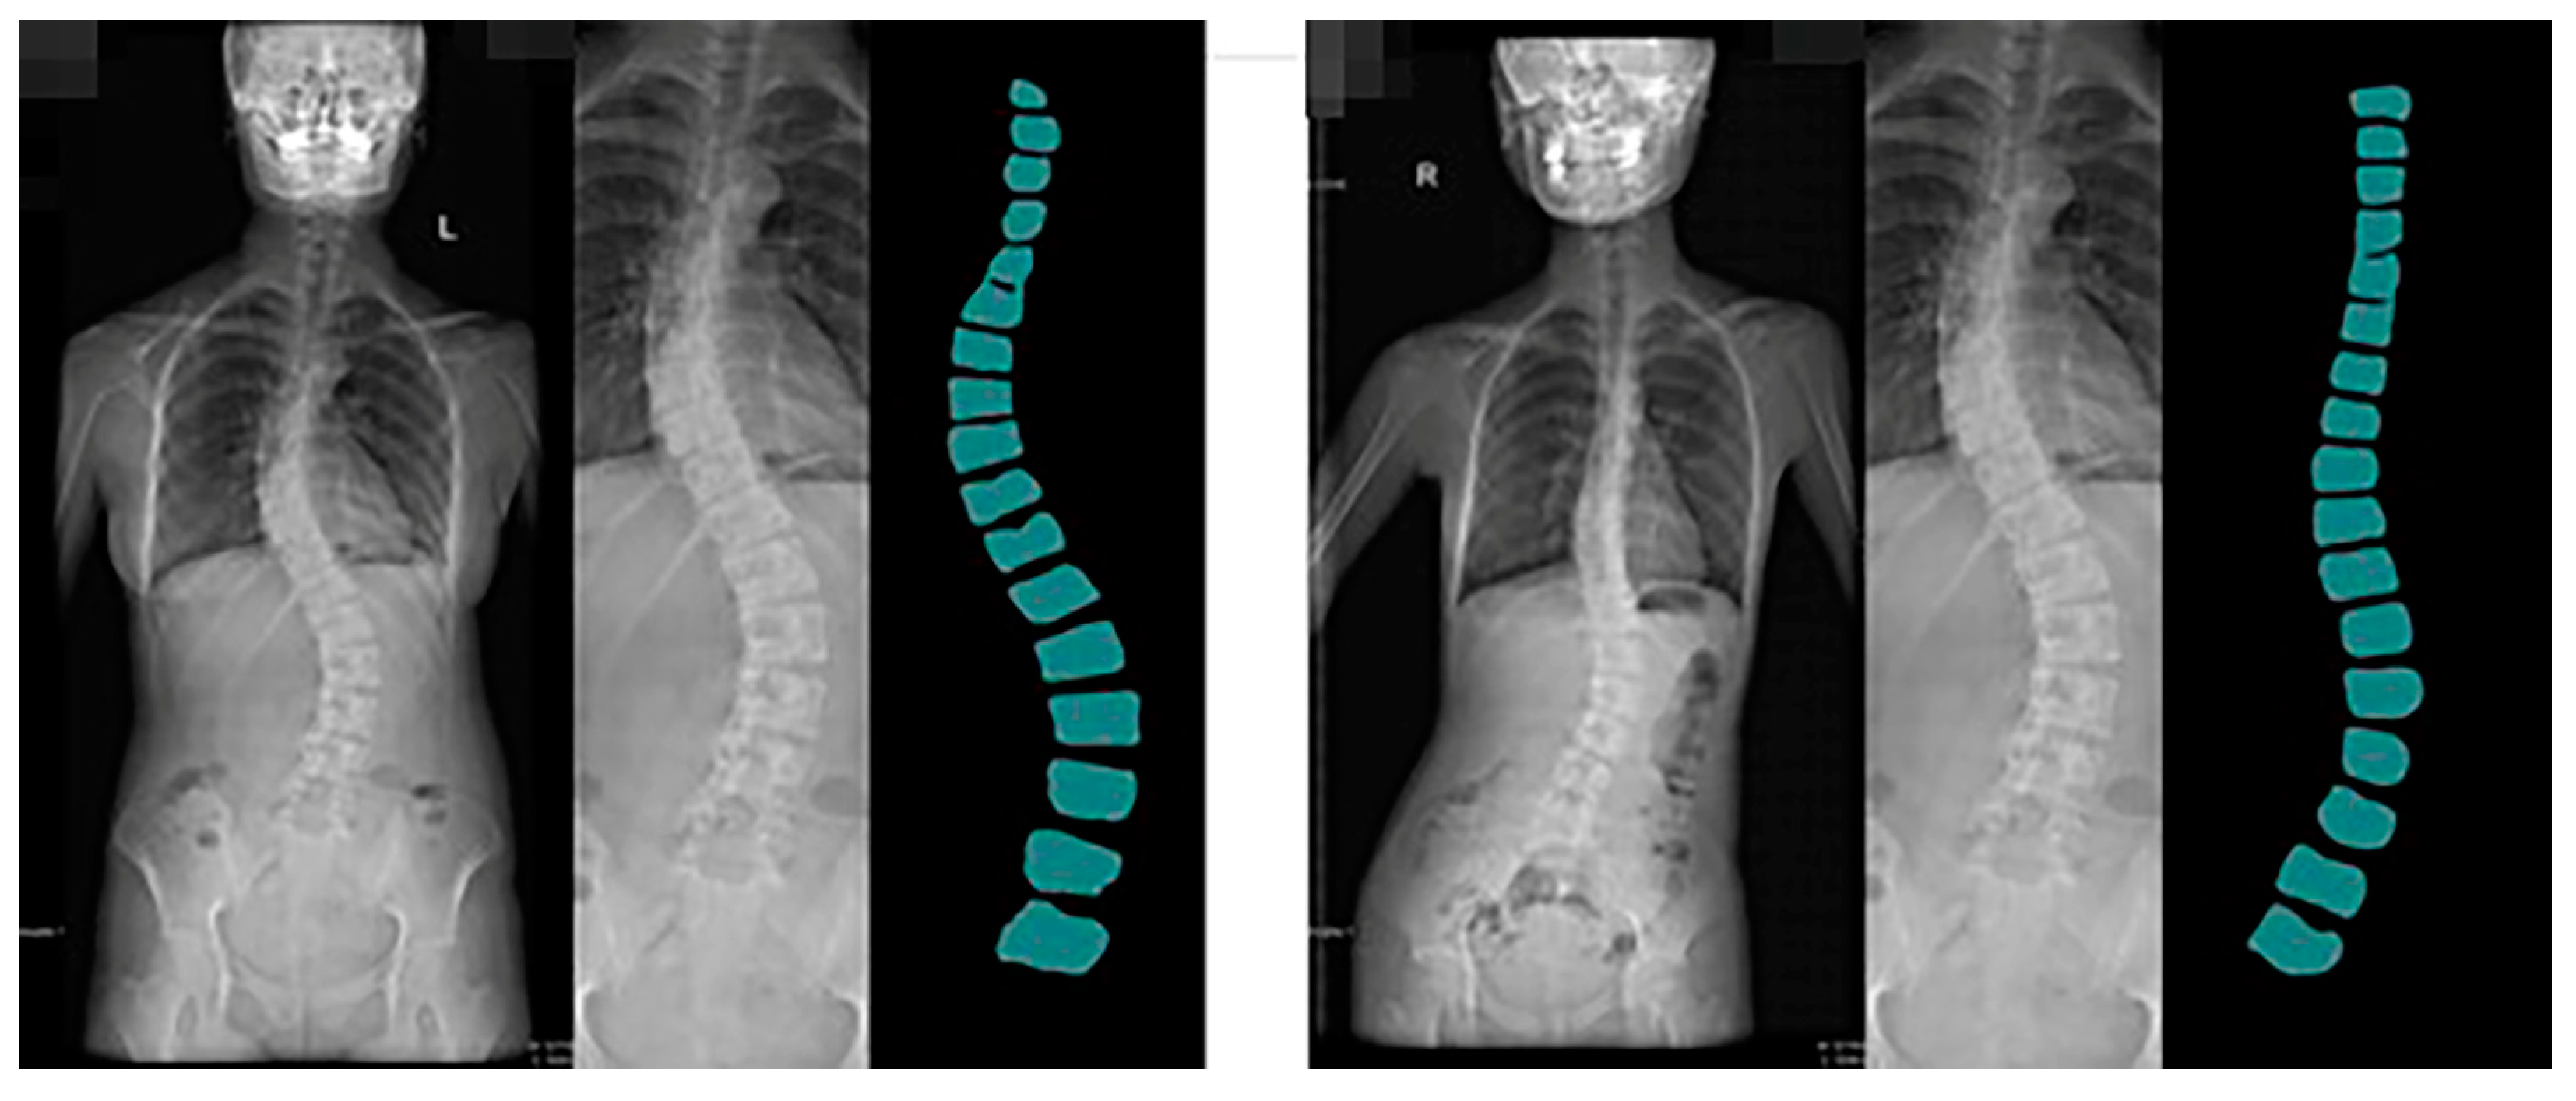

Guizhou Province is the most affected area by coal-fired fluorosis. The coal-burning type of ground fluorosis, and coal-burning polluted endemic fluorosis is a type of ground fluorosis unique to China in the world, affecting about 15 million people, with about 10 million people suffering from dental fluorosis and about 1 million people suffering from bone fluorosis. Fluorosis severely affects residents’ bone health and quality of life [54]. The spine dataset of the Guizhou branch of Beijing Jishuitan Hospital uses X-ray images of the spine medical images, which reflect the bone quality of the inhabitants of Guizhou province, China, between the ages of 18 and 70. Due to geological conditions and the level of economic development, middle-aged and elderly residents have poor height development and often suffer from a range of diseases, including scoliosis, which is particularly serious. This dataset was developed in collaboration with the Guizhou branch of Beijing Jishuitan Hospital. Many ortho X-ray medical images of residents in Guizhou province were retrieved to produce the dataset. Due to privacy and legal issues, this dataset cannot be made public, and this dataset is labeled by is manually labeled. The segmentation prediction results generated by CI-UNet are shown in Figure 16.

Figure 16.

The segmentation prediction results generated by CI-UNet.

Training datasets need to be increased, resulting in less-than-optimal predictive segmentation. In the future, we will invest more human and material resources to solve the problem of data volume labeling. At the same time, we will produce more datasets for the local high prevalence of diseases. Based on the predicted images obtained, we calculated the angle of curvature of the spine. We chose the internationally used Cobb [55,56] index for spinal curvature assessment. The Cobb angle is a standard method used to measure the degree of scoliosis. It determines the degree of scoliosis by measuring the lateral bending angle of two adjacent vertebrae. Specifically, the Cobb angle is derived from the angle between two vertical lines drawn from the upper to lower surfaces of the two vertebrae.

During the measurement, the physician selects the two most curved adjacent vertebrae, draws a vertical line on their upper and lower surfaces, and then measures the angle between these two lines. This angle is the Cobb angle. Usually, the greater the Cobb angle, the more severe the scoliosis.

The Cobb angle is commonly used to diagnose scoliosis in adults, children, adolescents, and other spinal deformities. It is one of the most important indicators to assess the degree of scoliosis and the choice of treatment options. We calculated the prediction results based on the principle of Cobb calculation. The predicted image Cobb calculation results are shown in Figure 17.

Figure 17.

The predicted image Cobb calculation results.